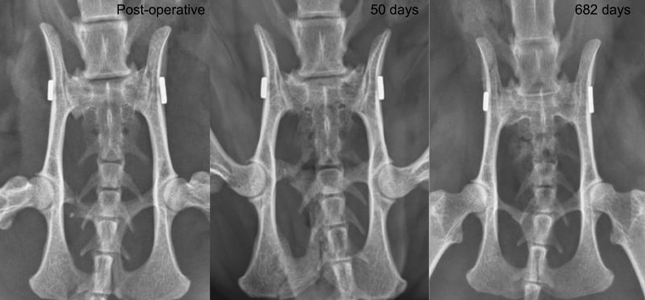

دامپزشک برای تشخیص شکستگی مفاصل از اسکن و اشعه ایکس استفاده کرده تا محل شکستگی رو به صورت دقیق مشخص و از طریق جراحی سلامتی گربه رو بهش برگردونه.

تصویربرداری از مفاصل

در این مرحله دامپزشک از طریق عکس برداری با روش های مختلف مثل سی تی اسکن گربه (CT)، رادیوگرافی برای گربه (X-ray)، ام آر آی گربه (MRI)، اولتراسوند به بررسی دقیق تر مفاصل پرداخته تا بتونه هرگونه ناهنجاری ساختاری، آرتروز، پارگی رباط، در رفتگی، شکستگی و... رو تشخیص بده، برای پیدا کردن مراکز تصویربرداری حیوانات اطراف خود میتوانید به صفحه لینک شده مراجعه کنید

سی تی اسکن و ام آر آی روش های خوب و دقیقی هستند که به دامپزشک کمک میکنه تا جزئیات مفاصل، تومور و بافت آسیب دیده رو تشخیص بده و از طریق اشعه ایکس هم میتونه رشد غیرعادی مفصل یا شکستگی و ضربه رو شناسایی کنه.